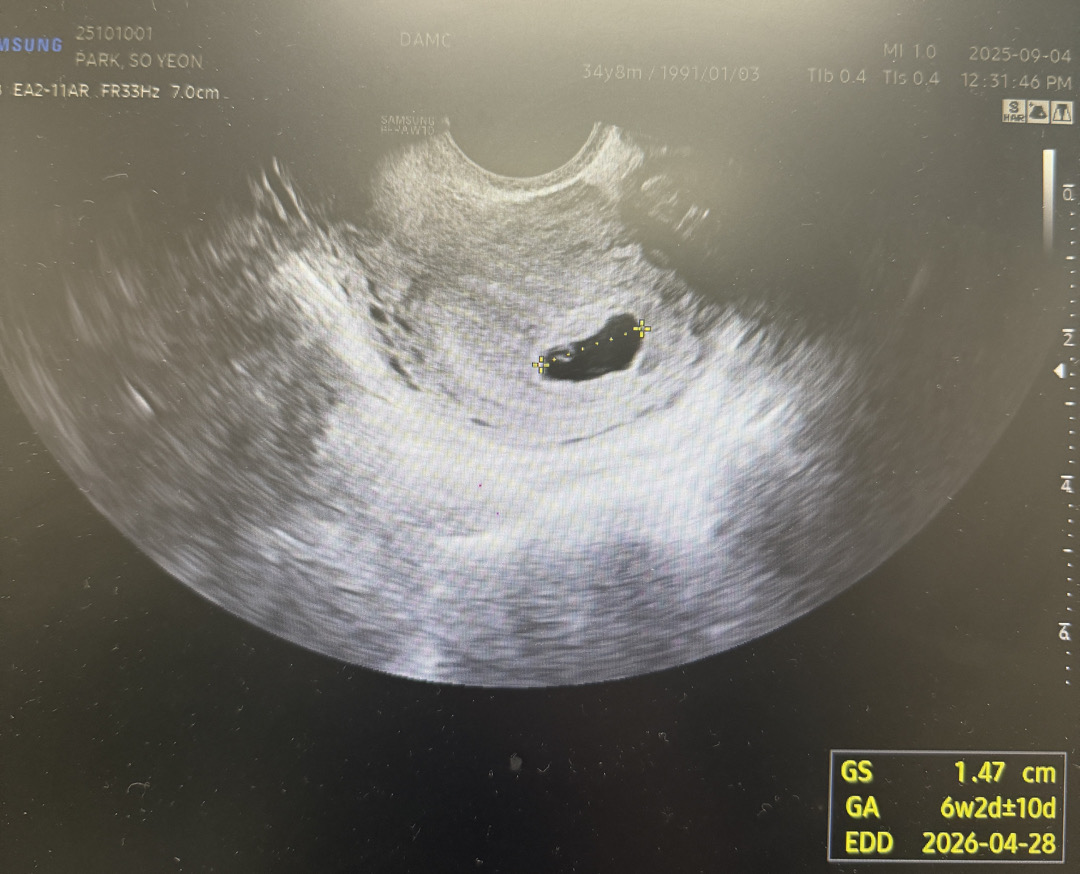

7주1일 초음파

처음 글쓰고 두번째네요 난황 못보고 쩔쩔매다 6주5일차에 극적으로 난황 확인하고 피검사 수치 더블링 잘되나 확인해보자해서 했는데 월요일 3529 수요일 3500 확인되고 오늘 아기 생겼나 확인하러 오라고 하셔서 갔다왔는데 아기집도 거의 못크고 아직도 난황만 덩그러니 있네요.. 교수님께서는 다음주 월요일 한번 더 보고 계류유산으로 수술할지 최종결정 하자고 하시고 마음이 많이 복잡하고 힘드네요.. 이러면 유산이 되고 있는걸까요..